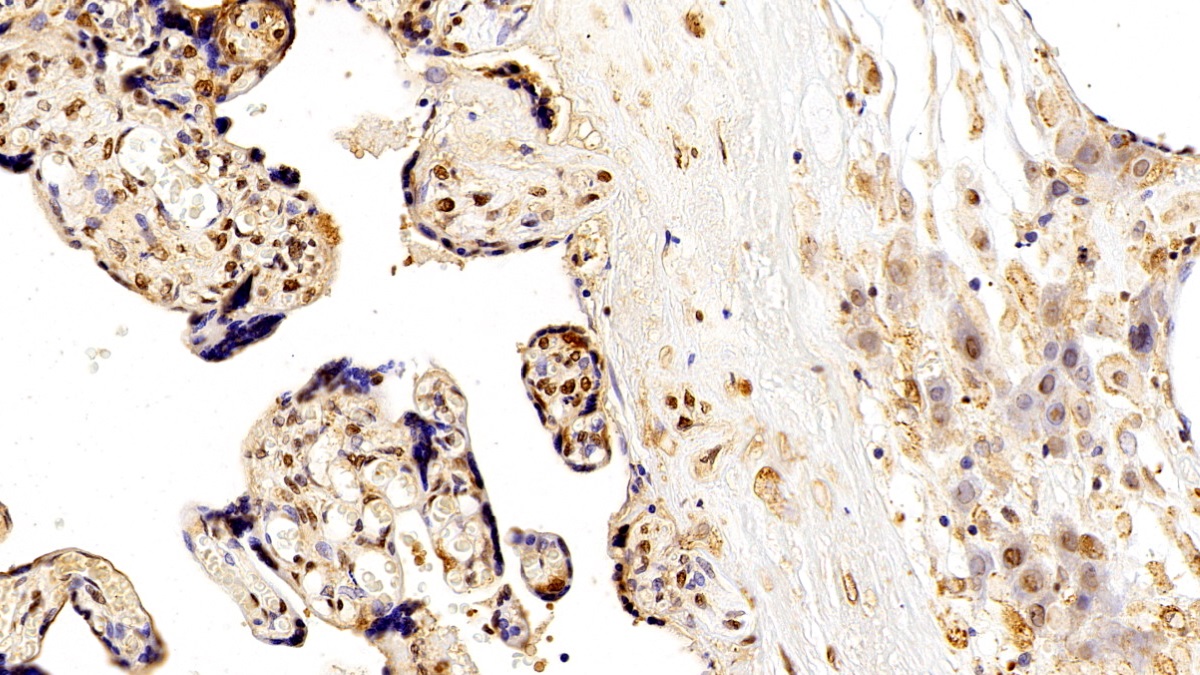

Использование высококачественных первичных антител является неотъемлемым условием получения точных и воспроизводимых результатов в современных научных исследованиях. Например, в рамках онкологического исследования удалось достоверно идентифицировать экспрессию белка PD-L1, что сыграло ключевую роль в оценке потенциальной эффективности иммунотерапии. Применение надежных антител обеспечило стабильность сигнала и высокую специфичность детекции, что позволило получить данные, пригодные для публикации в рецензируемых научных изданиях.